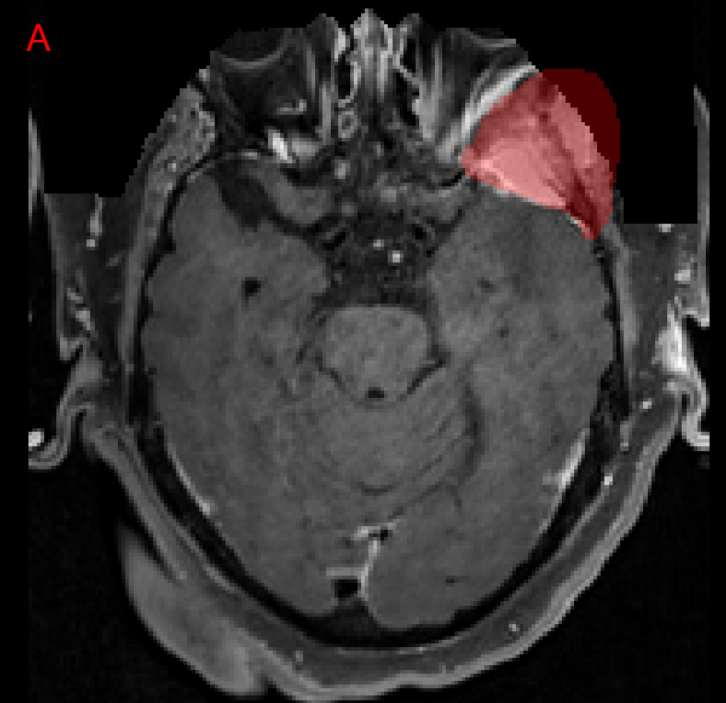

If the meningioma radiotherapy course was planned in the post-operative setting, then the target will comprise of the post-op resection bed and any residual ET on the T1c brain MRI (Figures 2 and 3).

Refer to caption

Figure 3: Panels A, B, and C showing a postoperative left parietal meningioma target volume (red) in the axial, sagittal, and coronal planes, respectively, as delineated by the treating institution.